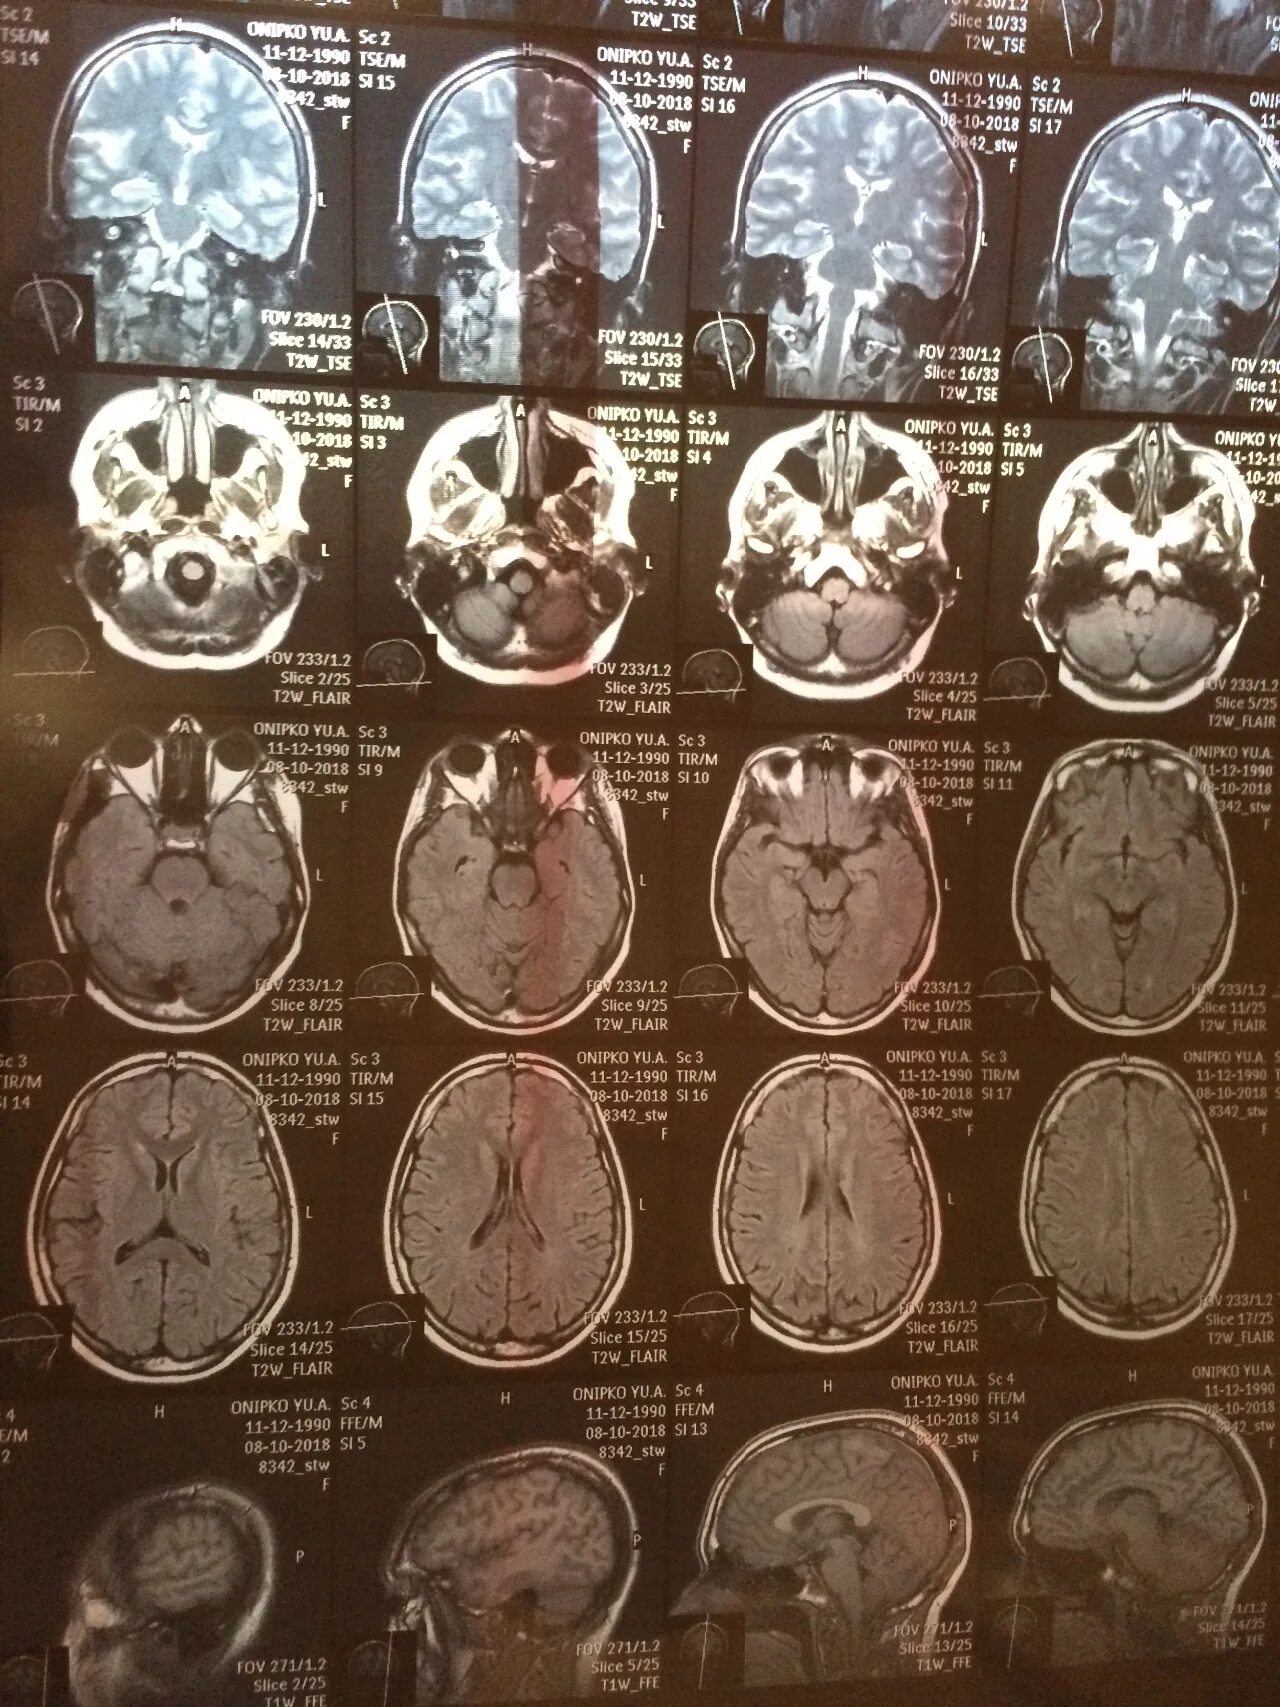

Мрт головного мозга и сосудов тула